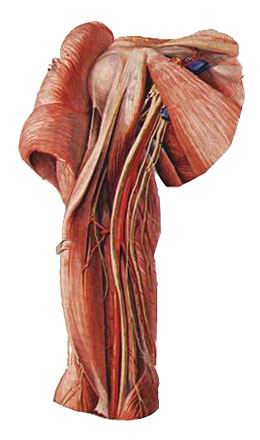

(1)肌皮神经

由臂丛外侧束发出,沿肱二头肌深面下行,肌支支配前臂前群肌,皮支布于前臂前外侧半皮肤。

(2)正中神经

由来自于外侧束和内侧束的两个根合成,伴肱动脉下行至肘窝,在前臂前群肌深浅两层之间下降,经腕管入手掌。肌支主要支配前臂大部屈肌,皮支主要布于手掌桡侧三个半指及相应手掌皮肤。损伤后表现为“猿手”。

(3)尺神经

由臂丛内侧束发出,初伴肱动脉下降,继而绕过尺神经沟至前臂伴尺动脉入手掌。肌支主要支配前臂尺侧一个半屈肌(尺侧腕屈肌和指深肌尺侧半,简称一尺半深)和大多数手肌。皮支主要分布手掌尺侧一个半指、手背尺侧二个半指及相应手掌、手背皮肤。肱骨髁上骨折最易损伤尺神经,表现为“爪形手”。

(4)桡神经

由臂丛后束发出,沿桡神经沟下行至前臂及手背。肌支主要支配臂和前臂后群肌及前群的肱桡肌。皮支主要布于手背桡侧两个半指及相应手背皮肤。损伤后表现为“垂腕”。

(5)腋神经

由臂丛后束发出,绕肱骨外科颈行向后外,肌支支配三角肌,皮支布于肩部皮肤。损伤后表现为“方肩”。